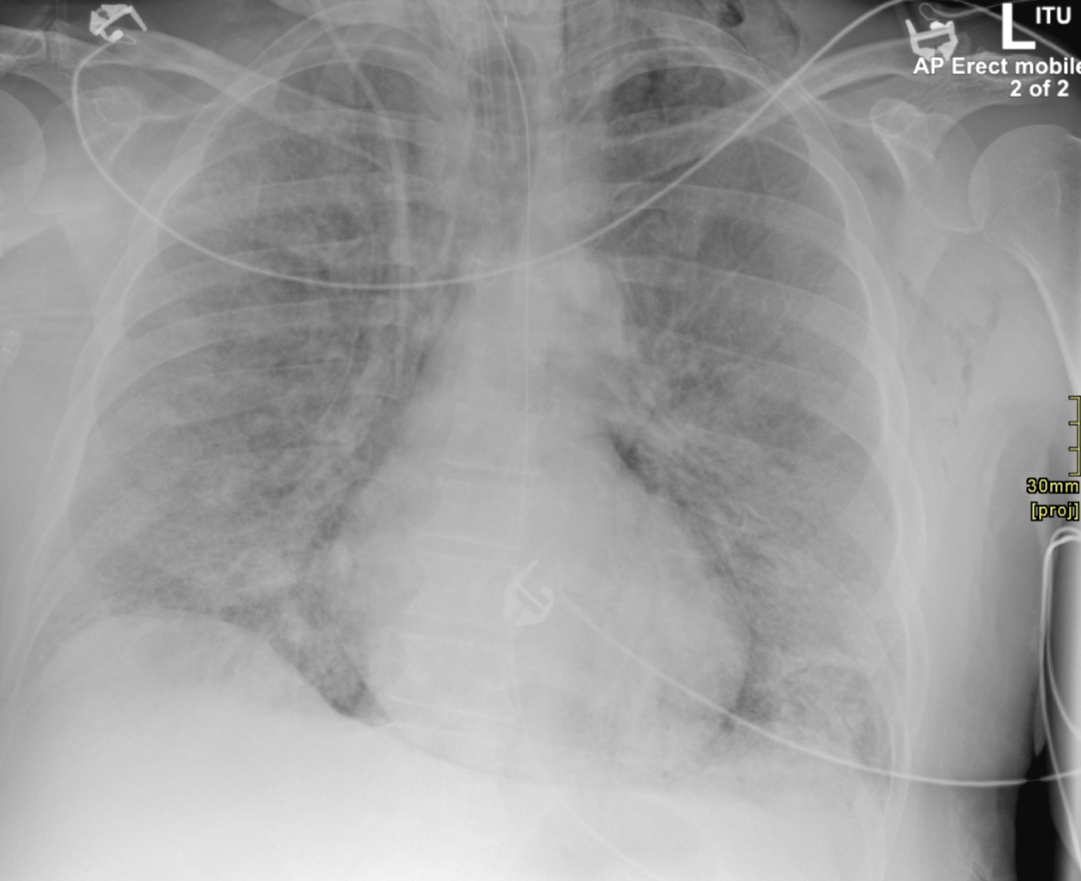

3. Pneumomediastinum barotrauma